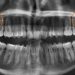

La gestación es una etapa hermosa en la vida de toda mujer, sin embargo, no está exenta de ciertas complicaciones bucodentales. Los cambios hormonales, no solo hacen que la futura madre esté más sensible o cambie bruscamente de humor. También alteran la normalidad de los tejidos que sostienen los dientes. Los elevados niveles de estrógenos y progesterona favorecen la inflamación de las encías y el sangrado durante el cepillado, dando paso a la formación de lesiones benignas como el épulis del embarazo.

El épulis del embarazado o granuloma gravidarum, es un tipo de épulis dental. Se caracteriza por un quiste, protuberancia o tumor benigno que aparece en el ligamento periodontal que une al diente con la encía. Por lo general, se presenta como una pequeña bola roja o púrpura con una consistencia blanda y una superficie lisa.

Es producto de la inflamación masiva de los tejidos gingivales y pese a su singular aspecto, en primera instancia no es doloroso. No obstante, con el paso del tiempo, empieza a generar molestias e incluso algo de dolor por el continuo contacto y el roce.

Se estima que, durante el embarazo, aumenta entre un 50% y un 100% la prevalencia de gingivitis en las mujeres. Esto, se debe a los cambios hormonales y a la especial incidencia de la progesterona. Tales efectos, aunado a una mala higiene bucal y hábitos nocivos previos, como el consumo de tabaco, incrementan el riesgo de padecer épulis dental.